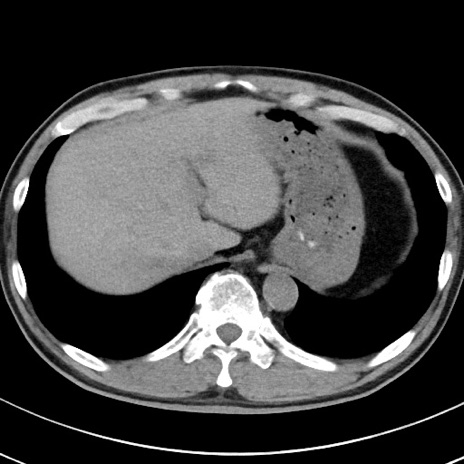

【腹部TIPS】症例29 参考症例 CT(横断像)

症例

70歳代男性